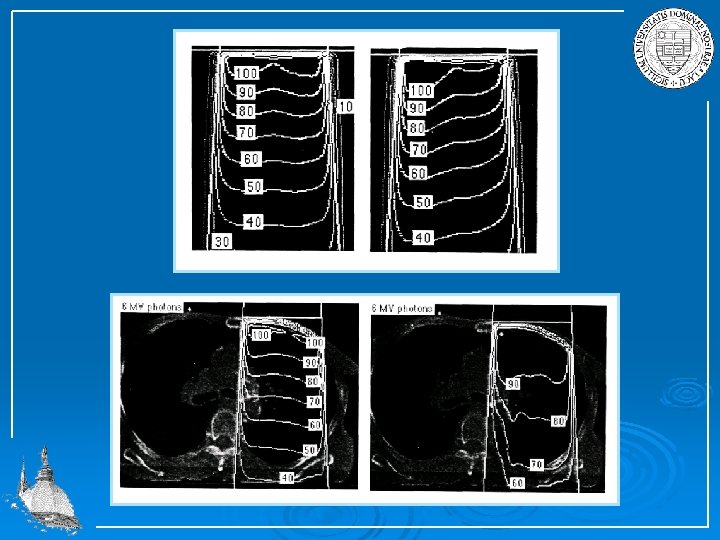

Within the area A each point at a certain depth d receives the same dose ISODOSE. Isodose profiles are plotted in terms of the percentage depth dose %DD because absolute dose measurements are difficult. The percentage depth dose is the absorbed dose at a given depth d expressed as a percentage of the absorbed dose at a reference depth dmax along the central axis of the beam. In figure above the percentage depth dose at point A is 75 %. Isodose charts are usually plotted in increments of 10 %. They depend on the beam geometry and the various absorption effects within the body tissue.

Examples of isodose profiles For electron beam the percentage depth dose increases with depth, the maximum range depends on the initial energy of the electron beam. The isodose profile widens rapidly due to wide angle scattering.

For heavy ion beam the profile remains well defined but the percentage depth dose increases rapidly at well localized position due to Bragg curve behavior plus decay radiation from on line produced activities.

For radiation the percentage depth dose peaks at small depths but ranges deeply into the tissue proportional to the absorption coefficient.

The angle scattering is small, the beam profile and therefore the isodose profile remains well defined. Cobalt 60 4 Me. V 6 Me. V 15 Me. V